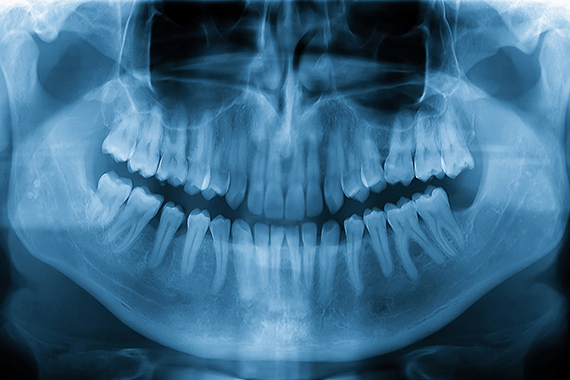

親知らずの抜歯や顎の痛み、口内のできものなど、口腔外科ではお口まわりの外科的な処置を専門的に行います。当院では、長久手エリアにお住まいの患者さんが安心して治療を受けられるよう、事前の診査・説明を丁寧に行い、不安の少ない対応を心がけています。外科的な処置に対して不安があるかたも、まずはお気軽にご相談ください。

親知らずの抜歯

斜めや横向きに生えた親知らずは、痛みや腫れの原因になります。状態を確認し、安全性に配慮した抜歯を行います。